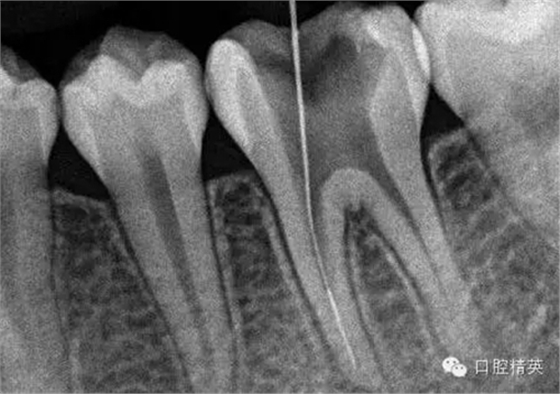

8,找到后,直接用超聲根管搓15號帶出斷針。。。

9,斷針取出術(shù)后X-P,RCT待續(xù)。。。